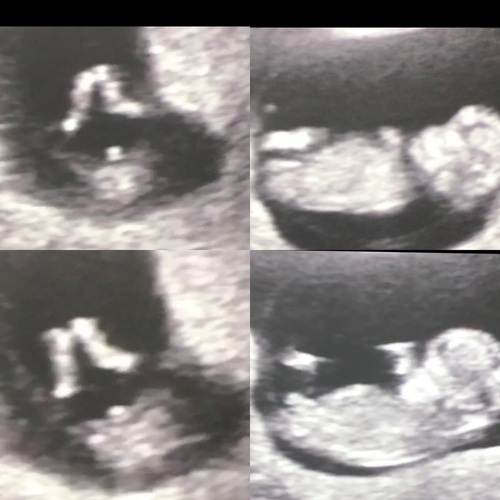

Weet iemand het van ons 13 weken meisje of jongen? 馃檭

Als het op de ramzi theorie is denk ik een meisje

Als is goed die twee streepjes welke jij zie dat zijn schaamlipjes had precies zelfde echo. En bij mij wordt het meisje 馃グ

Dacht 3 streepjes meisje 馃槀 geen idee moet volgende week dinsdag weer dan ben ik 11 weken kijke we nog is